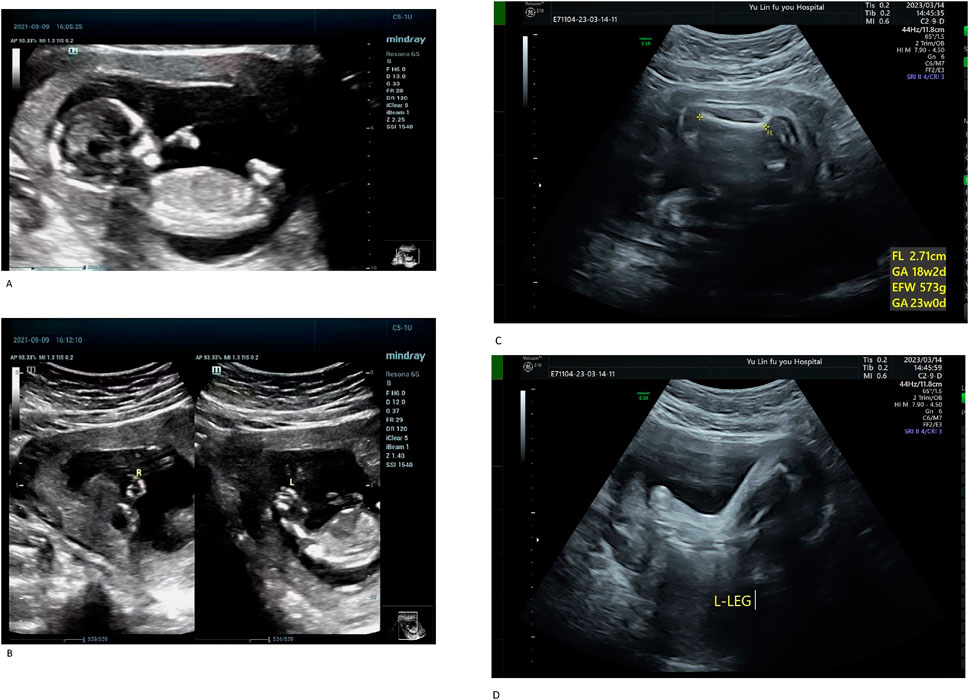

The proband (III-1) was a male fetus from the patient’s first pregnancy. At 14 weeks of gestation, prenatal ultrasound revealed significant shortening of all four limbs, abnormal hand positioning suggestive of bilateral radial aplasia, fixed lower limb posture, and bilateral clubfoot (Figures 1A,B). Additionally, reversal of the a-wave in the ductus venosus was observed. Due to multiple severe structural anomalies, the pregnancy was terminated. The fetus weighed approximately 100 g at delivery and exhibited no other discernible malformations.

Figure 1. (A) Systemic fetal ultrasound results of the proband (III-1). (B) Systemic fetal ultrasound results of the proband (III-1). Ultrasound examination revealed shortened limbs, abnormal positioning of both hands (suggestive of bilateral radial aplasia), fixed posture of both lower limbs, and bilateral clubfoot. Reversed a-wave in the ductus venosus was also observed, leading to pregnancy termination (A,B). (C) Systemic fetal ultrasound results of III-3. (D) Systemic fetal ultrasound results of III-3. At 26 weeks of gestation during her third pregnancy, Case III-3 underwent a level II ultrasound, which revealed shortened limbs, bilateral clubfoot, and an enlarged gallbladder (C,D).

The proband’s mother (II-3) is a 25-year-old woman with a height of 140 cm, an arm span of 115 cm, and a weight of 51.5 kg. Her height was notably greater than her arm span. She exhibited short limbs with bilateral elbow contractures and restricted elbow extension, reaching approximately 150° at full extension. The forearms were slightly flexed with pronation deformity. Cognitive development and intelligence were normal. The palmar ATD angle was greater than 45°. She is gravida 3, para 0, and was referred to our hospital at 26 weeks of gestation for prenatal genetic evaluation owing to a family history of fetal structural anomalies and recurrent pregnancy loss. Her second pregnancy (III-2) resulted in a biochemical pregnancy, with the fetal sex undetermined. In her third pregnancy (III-3), a prenatal ultrasound at 26 weeks revealed limb shortening, bilateral clubfoot, and gallbladder enlargement (Figures 1C,D). On 15 March 2023, cordocentesis was performed for prenatal genetic testing, followed by elective pregnancy termination.